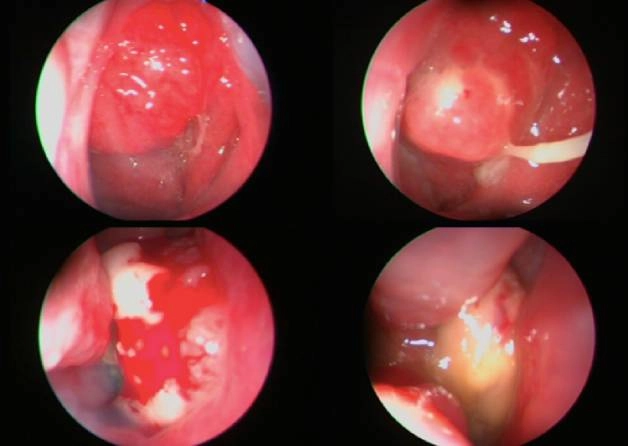

Hình ảnh nội soi khi bị ung thư tại vòm mũi họng